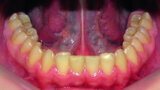

Orthodontic management of maxillary lateral incisors agenesis